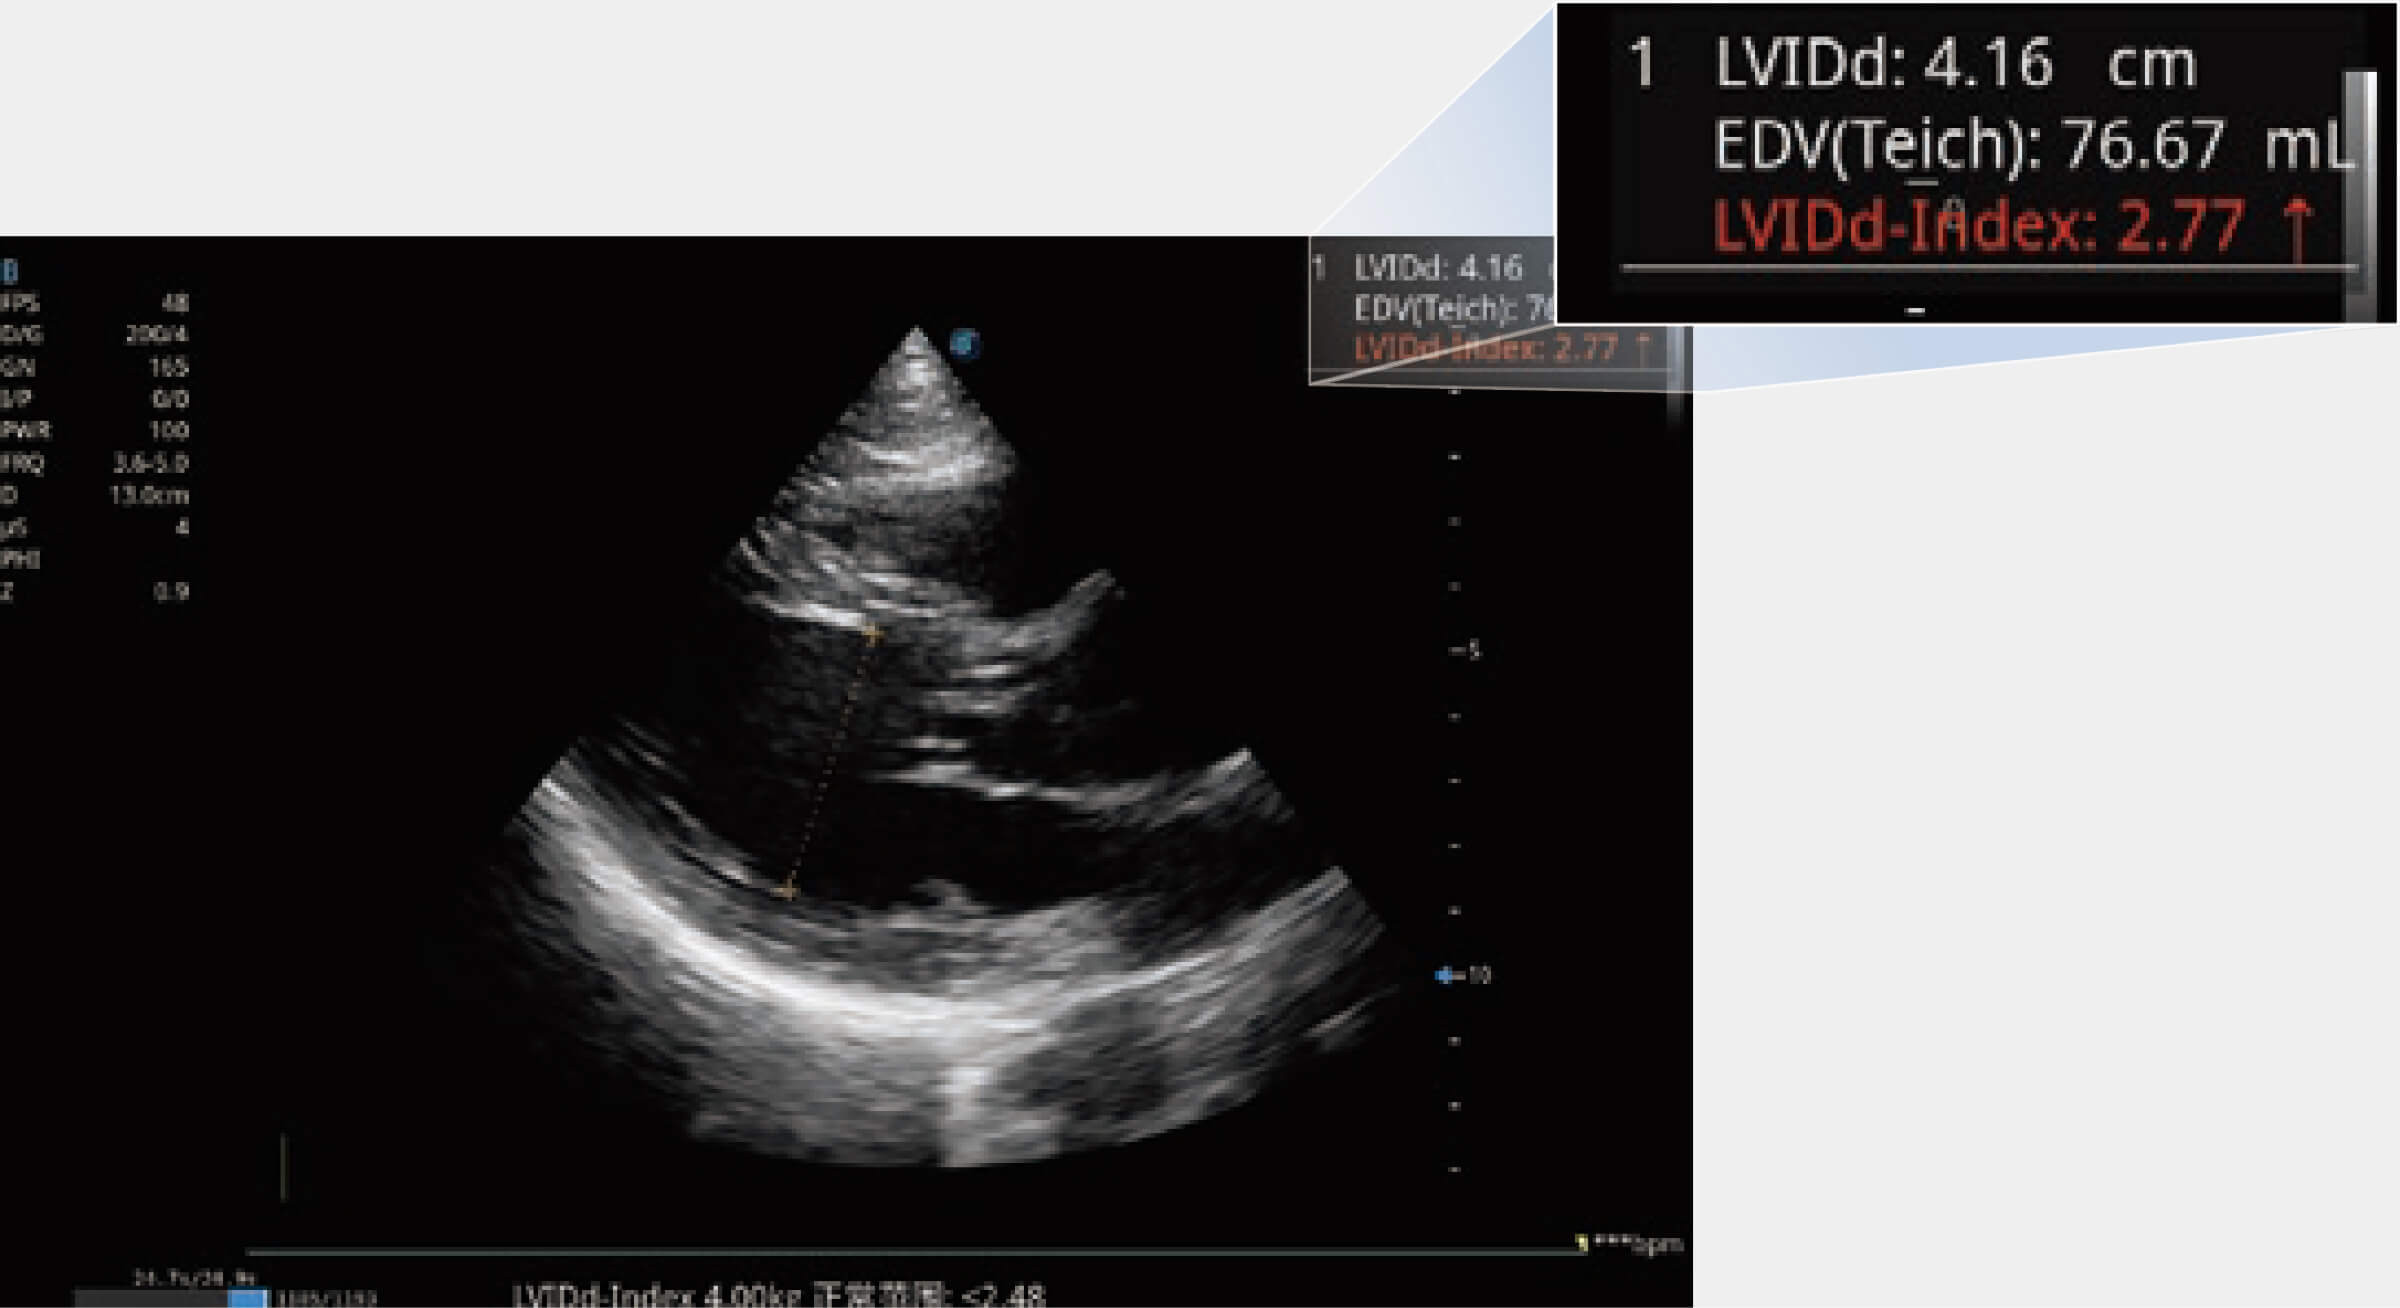

當(dāng)心臟測(cè)量結(jié)果超出正常范圍時(shí),可實(shí)時(shí)預(yù)警提示動(dòng)物醫(yī)生,減少疾病漏診概率。

ProPet 70專(zhuān)為動(dòng)物醫(yī)生設(shè)計(jì),對(duì)不同的動(dòng)物體型和生理結(jié)構(gòu)作出了針對(duì)性的優(yōu)化。通過(guò)動(dòng)物影像專(zhuān)用軟件,可滿(mǎn)足個(gè)性化的應(yīng)用需求,幫助動(dòng)物醫(yī)生獲得更精確的診斷數(shù)據(jù)。